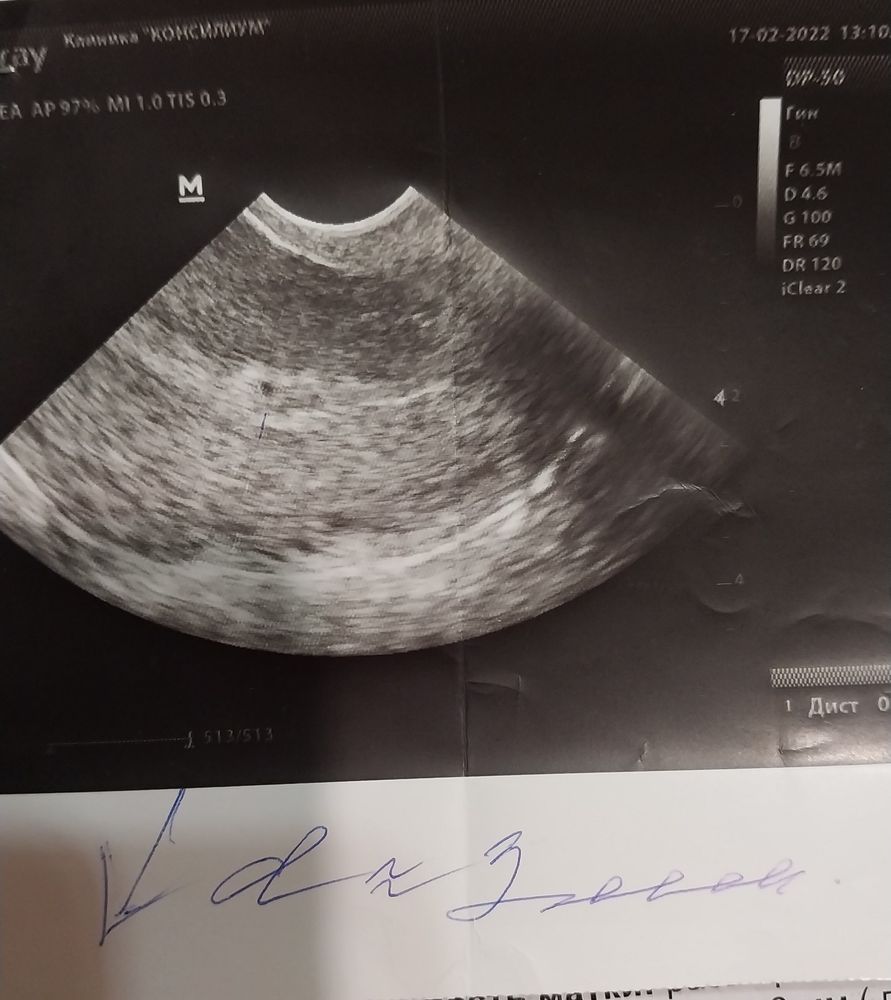

Но Я была бы не Я, если бы не пошла перепроверять все данные в другую клинику…было это через 3 дня -17.02. И тут случилось чудо...не иначе !!! В матке нашли пя 2-3 мм, при том что хгч был накануне всего 756 ! То есть за 4 с половиной дня он только увеличился в 2 раза (промежуточный результат от 15.02 был 565 ) Тогда я еще не знала что пя можно увидеть лишь при хгч больше 1000, хотя может он и увеличился за сутки примерно до этих чисел. Сказать что я снова выпала в осадок ничего не сказать. При всем при этом врач узи обнадеживала наставлениями что на терапии есть все шансы на прогресс и что она сама якобы 2 естественные беременности без жт выносила ! Ну прям чудо господне, вспоминала я потом ее слова ! Но жт так и не было найдено ! И факт маленького увеличения хгч и день цикла врача не смутили, приходи в первых числах марта уже будет видно эмбрион сказала она. Супер думаю при неизвестно каком дпо через 10 дней она уверенна что уже появятся зачатки плода…Вроде опять же надо радоваться что хоть пя нашли, что не вб, но я не унималась ! Внутри все предательски твердило что все не так идет как должно быть...

Вот мой эмбрион, а говорили анэмбрионию. Я понимаю что замер, но диагноз неверный сказали, а при хорошем аппарате увидели.